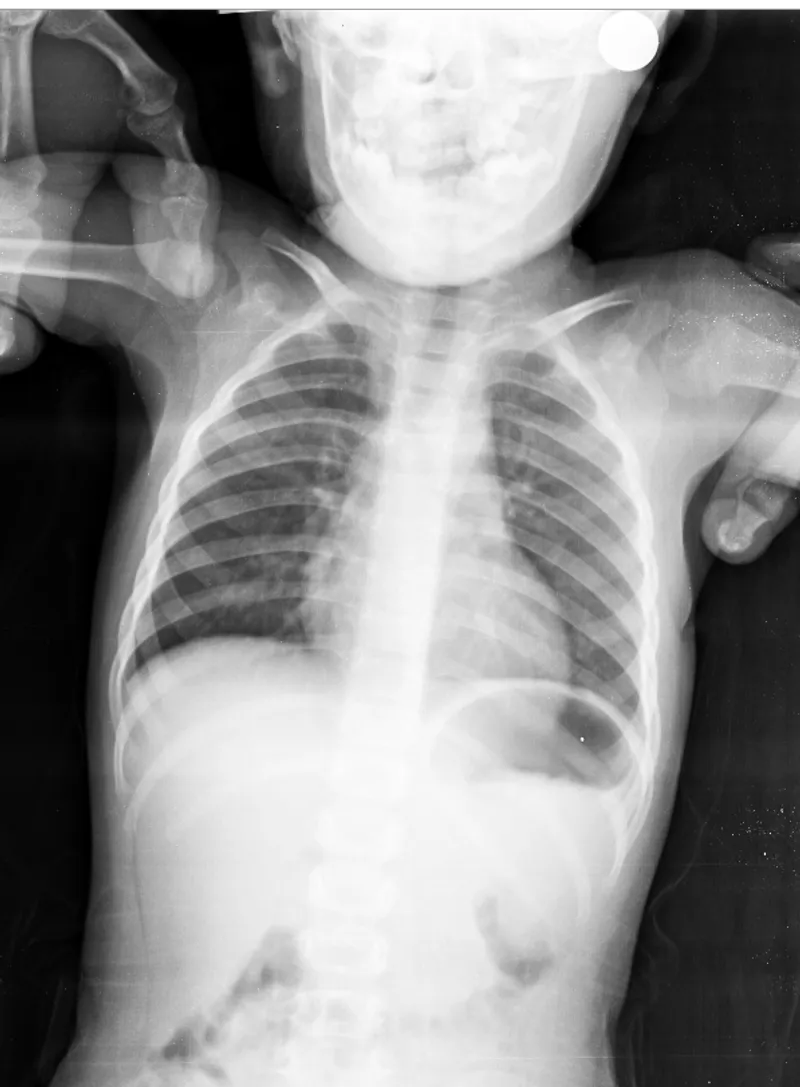

Bu filme göre antibiyotik kullanmali miyiz ?

Burnu akiyor öksürük var 10 gundur devam ediyor. Ilerleme yaparmı